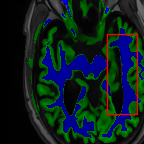

Sparsity LI 2D CNN 3D CNN Ours GT

4 Refer to caption (a) 0.6787/0.7972 Refer to caption (b) 0.8143/0.8776 Refer to caption (c) 0.8190/0.8714 Refer to caption (d) 0.8664/0.9085 Refer to caption (e) GM/WM

Refer to caption (f) 0.6808/0.7161 Refer to caption (g) 0.8103/0.8631 Refer to caption (h) 0.7950/0.8606 Refer to caption (i) 0.8598/0.9115 Refer to caption (j) GM/WM

Figure 6: Visual comparison of gray matter (Green)/white matter (Blue) segmentation over different methods, with respective DICE scores listed under the images.

In Fig. 6, we demonstrate the advantage of the proposed method in brain matter segmentation. It is clear that although 2D and 3D CNN generates visually plausible interpolation as presented in Fig. 5, the brain matters are easily misclassified due to incorrect anatomical structures and blurred details.